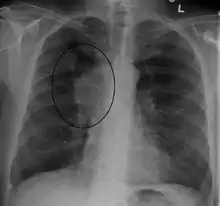

A CXR of a person with lung cancer which was causing superior vena cava syndrome.

The main techniques of diagnosing SVCS are with chest X-rays (CXR), CT scans, transbronchial needle aspiration at bronchoscopy and mediastinoscopy.[5] CXRs often provide the ability to show mediastinal widening and may show the presenting primary cause of SVCS.[5] However, 16% of people with SVC syndrome have a normal chest X-ray. CT scans should be contrast enhanced and be taken on the neck, chest, lower abdomen, and pelvis.[5] They may also show the underlying cause and the extent to which the disease has progressed.[5]